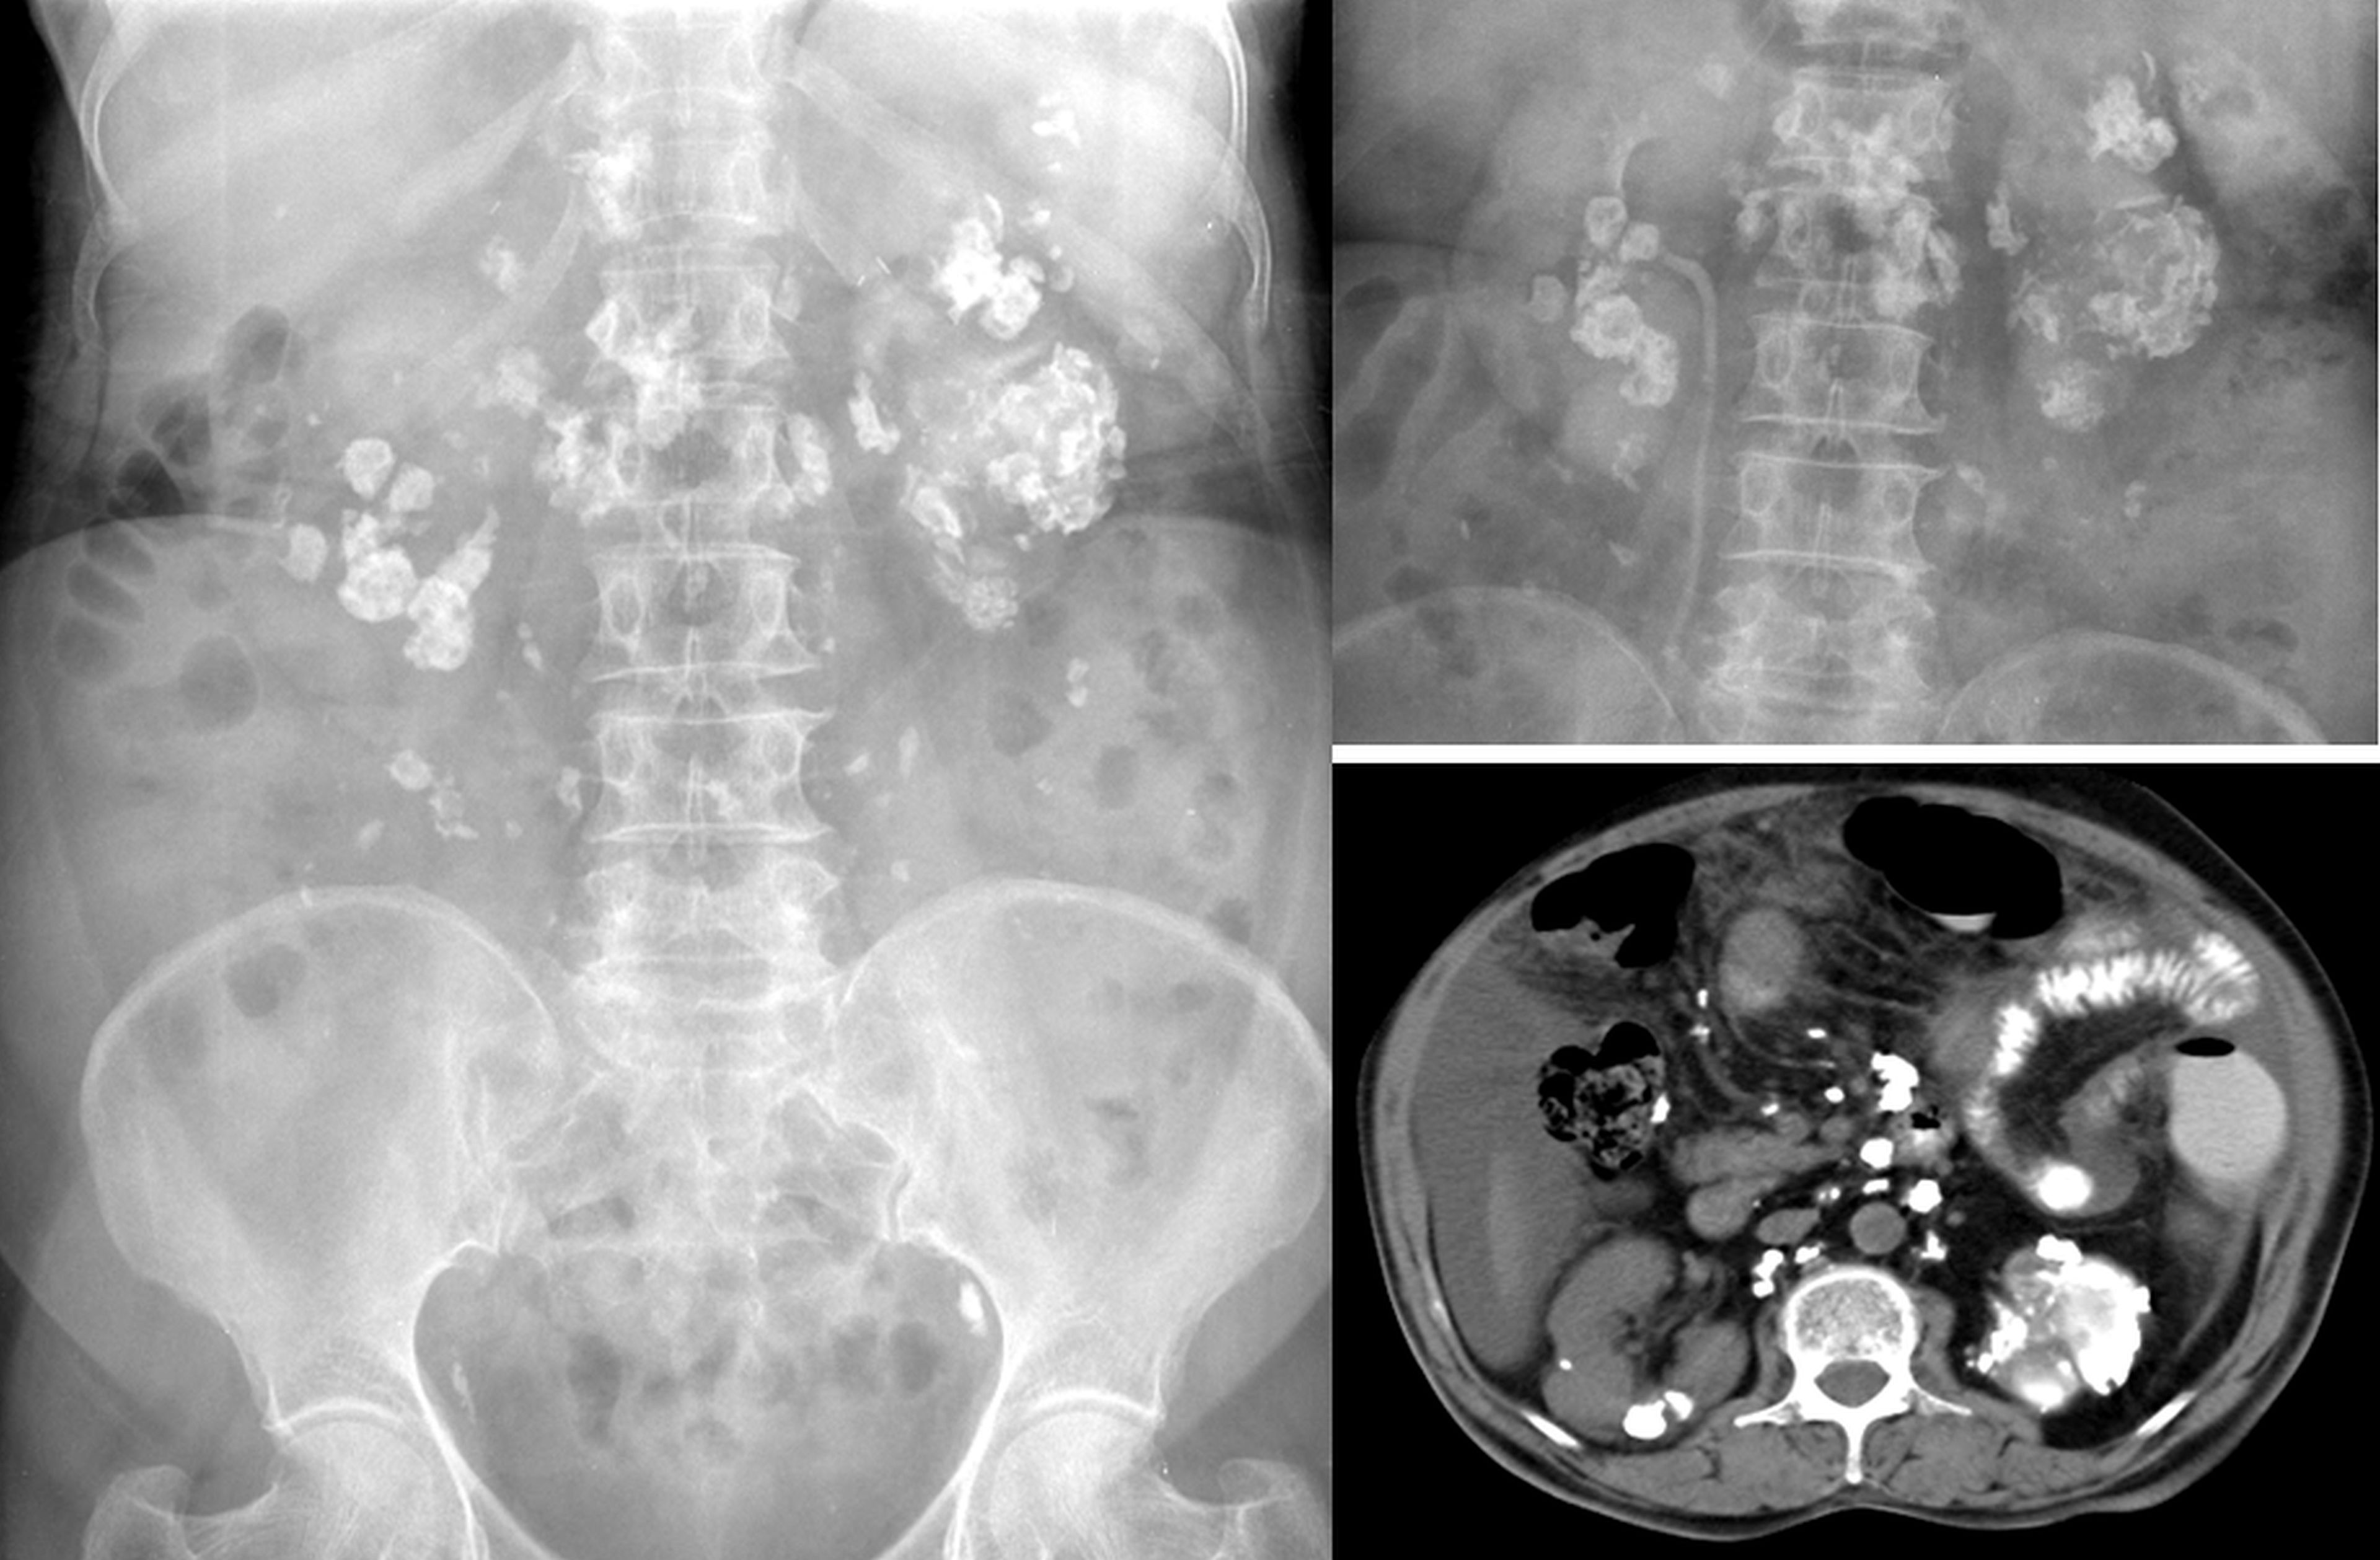

Tuberculosis of urinary tract